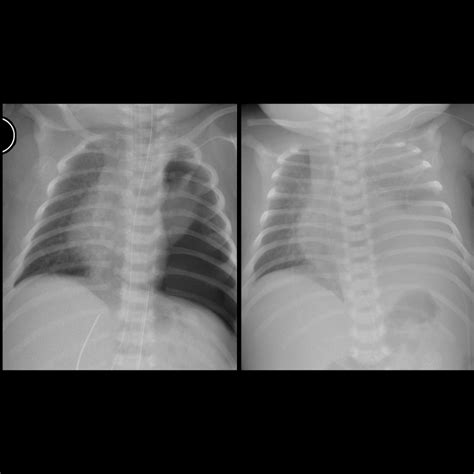

Lung Impact Pulmonary hypoplasia (underdeveloped lungs).

To fully grasp what is CDH, one must understand how it physically alters a newborn's anatomy. The diaphragm is essential for normal breathing. When a hole exists in this muscle, the vacuum pressure changes within the thoracic cavity. As the abdominal organs migrate into the chest, they compress the developing lungs, hindering the branching of the airways and the development of blood vessels.

The severity of CDH is largely determined by the timing of the defect during gestation and the specific organs that migrate into the chest. In many cases, the heart may also be pushed out of its normal position, which can further impact circulatory function at birth. This combination of underdeveloped lungs and potential circulatory strain is why babies born with CDH require specialized neonatal care immediately upon delivery.

While the surgical repair closes the anatomical gap, survivors of CDH often require ongoing medical monitoring. Because the lungs were compressed during a critical growth period, some children may experience long-term respiratory challenges. Common follow-up areas include:

• Pulmonology: Monitoring lung function and addressing potential chronic breathing issues.